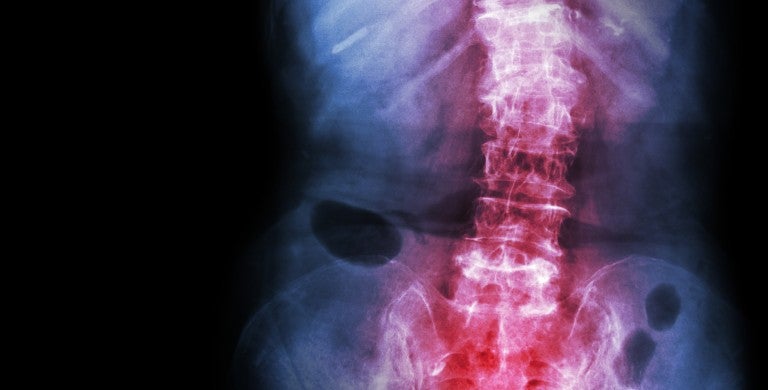

Spondylolisthesis

Spondylolisthesis can make everyday movements painful. But you don’t have to live with the pain. At LVHN, you’ll receive comprehensive care, from a precise diagnosis to advanced treatment and close follow-up. We treat hundreds of patients every year, giving us a high level of skill and experience in diagnosing and treating spondylolisthesis.

In spondylolisthesis, one bone in your back (vertebra), slides forward over the bone beneath it. This usually happens in the lower spine. The sliding squeezes your spinal cord or nerves. Spondylolisthesis can be caused by: